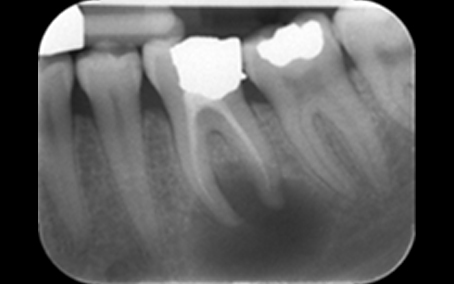

Radiograph 1 2023

Radiograph 2 2023